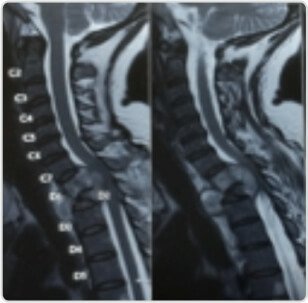

একজন 45 বছর বয়সী মহিলা D1-D2 পটের মেরুদণ্ড এবং কর্ডের সংকোচনের সাথে উপস্থাপিত হয়েছিল, তার মূত্রাশয় অসংযম সহ B/l নিম্ন অঙ্গের 2/5 দুর্বলতা ছিল।

MRI – D1, D2 কর্ড সংকুচিত করে D2 সংগ্রহের সম্পূর্ণ পতনের সাথে জড়িত